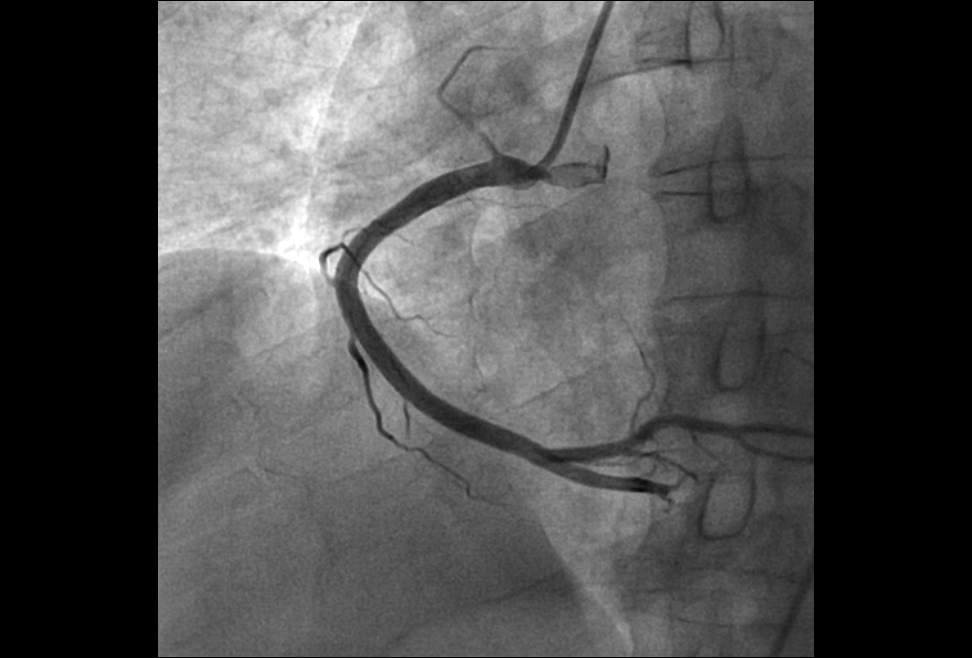

1.心血管介入手术治疗:可以完成冠状动脉造影术,PTCA支架术,二尖瓣球囊扩张术,射频消融术,起搏器植入术,先天性心脏病介入治疗,冠状动脉腔内溶栓术等微创介入手术。

病患的右冠狭窄 通过DSA支架植入 有冠状动脉恢复正常供血,病人病情缓解